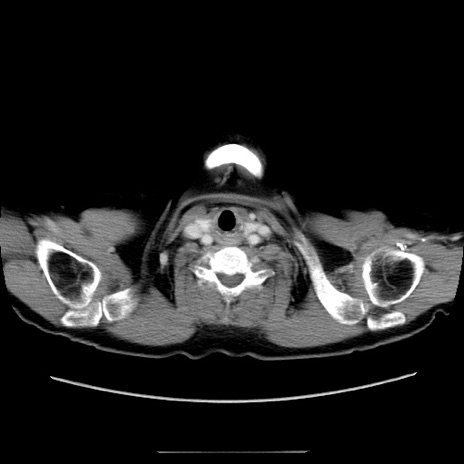

症例5(横断像)

【症例】70歳代女性

【主訴】お腹が張る

【現病歴】1週間くらい前から腹部膨満の自覚あり。昨日夜から増悪したため、本日救急外来受診。

【身体所見】意識清明、BT 36.5℃、BP 165/106mmHg、HR 80bpm、SpO2 98%、腹部:膨満、軟、自発痛・圧痛なし、触診にて不快感あり、腸蠕動音:減弱

【データ】WBC 12600、CRP 1.04